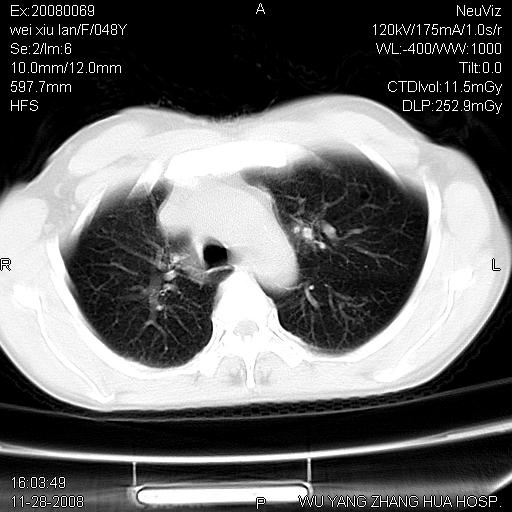

左下肺不张、膈膨升,胸腔胃

1.左侧隔膨升

2.左下肺炎性改变

左膈顶及肋膈角均上移,膈面光滑,考虑左膈肌麻痹